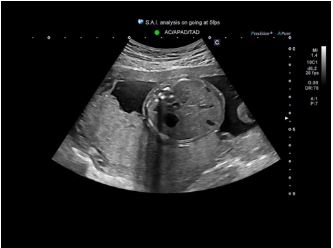

Індикації в акушерстві з підтримкою алгоритму глибокого навчання* допомагають ідентифікувати стандартні анатомічні структури для пришвидшення робочого процесу та посилення рівномірності результатів обстеження.

Автоматизоване відстеження та

підтримка вимірювань за допомогою ШІ може допомогти покращити послідовність

і ефективність робочого процесу в широкому діапазоні застосувань.